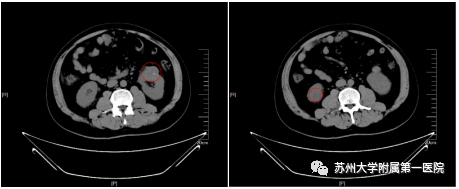

近日,家住安徽枞阳县的43岁王先生(化名) 因腰部胀痛不适两周到当地医院就诊 查CT显示:双肾占位,左侧4.5cm,右侧1.5cm 考虑恶性肿瘤! 左侧肾癌的RENAL评分达到了8A 手术难度相当大! 由于双侧肾都有肿瘤,大小位置都有差异 当地就诊医生建议患者行分时分侧肾部分切除 (图中红色圈标出部分为肾肿瘤) 患者了解到苏州大学附属第一医院泌尿外科机器人手术团队治疗高难度肾癌经验丰富、技艺精湛,于是怀揣着希望来到了我院就诊。 入院后,我院泌尿外科机器人团队 在黄玉华教授及浦金贤教授的指导下 进行了病例讨论,仔细读片,商讨手术方案 团队考虑到患者为中青年,是家庭顶梁柱!分时分侧行肾部分切除术虽然是最稳妥的手术方式,但……无疑会给这个家庭带来极大的负担,这个家庭可能有很长一段时间没有收入来源! 由于肿瘤位于双侧,普通的腹腔镜手术必然不能完成此次手术,综合考虑手术及风险、经济原因等因素后,泌尿外科机器人团队制定了机器人辅助下双侧肾癌一期肾部分切除术的治疗方案,力求在治愈肿瘤的同时为患者尽可能多的保留双肾功能,用最小的创伤获得最大收益。经团队讨论,该手术将由浦金贤教授主刀完成手术。 手术日一早,机器人团队完成查房后就跟随两位教授赶到了手术室,与手术室巡回护士赵茹一同核查达芬奇机器人手术设备各项运行情况,以保证手术顺利运行。 在手术室嵇富海主任带领的麻醉医师团队合作下,有条不紊的完成麻醉,团队医生先在患者腹部打孔安装达芬奇机械臂,主刀医生浦金贤教授则在距离手术台2米左右的控制台前,熟练控制着操作杆和脚踏,通过传感器让机器人的机械臂配合默契的完成整台手术,成功切除患者双侧肾肿瘤,最大限度的保留双侧正常肾脏组织,出血量极少,效果满意。 (图为手术中切除的肿瘤) 黄玉华主任介绍道 达芬奇手术机器人(da Vinci Robotic Assisted Laparoscopic Surgery)在泌尿外科手术中优势明显,这个患者为双侧肾癌,位置及大小都有明显差异,特别是左侧肿瘤位于腹侧肾门部,位置刁钻、手术难度大。普通腹腔镜处理难度、风险巨大。 正是考虑到达芬奇机器人的优点,我们成功地在短时间内一期手术切除患者双侧肾肿瘤,保留双侧正常肾脏,术中出血少、缝合满意,使患者能够在短时间内恢复正常,同时节约了患者的费用。这次高难度手术的成功完成,标志附一院泌尿外科迎来了一个崭新的医疗微创时代,手术水平达到了先进的国际水平。 “达芬奇”手术机器人可广泛应用于泌尿外科、妇产科、普外科、胸外科等多个外科手术领域,更值得期待的是,远程手术概念已初具雏形,或许不久的将来,手术医生可以通过控制平台为千里之外的患者实施手术治疗。第四代“达芬奇”代表了目前全球手术机器人的高水准,开启了苏州肿瘤外科治疗领域新纪元,为苏州人民享受全球新科技医疗服务提供了机会和便捷。 擅长疾病:泌尿系统肿瘤及前列腺疾病和泌尿系统结石的诊治。 专家门诊: 十梓街院区:周一全天 总院:周二全天 擅长疾病:泌尿外科和男性老年的常见病和疑难杂症。 专家门诊: 十梓街院区:周二上午 总院:周一上午专家门诊;周一下午高级专家门诊